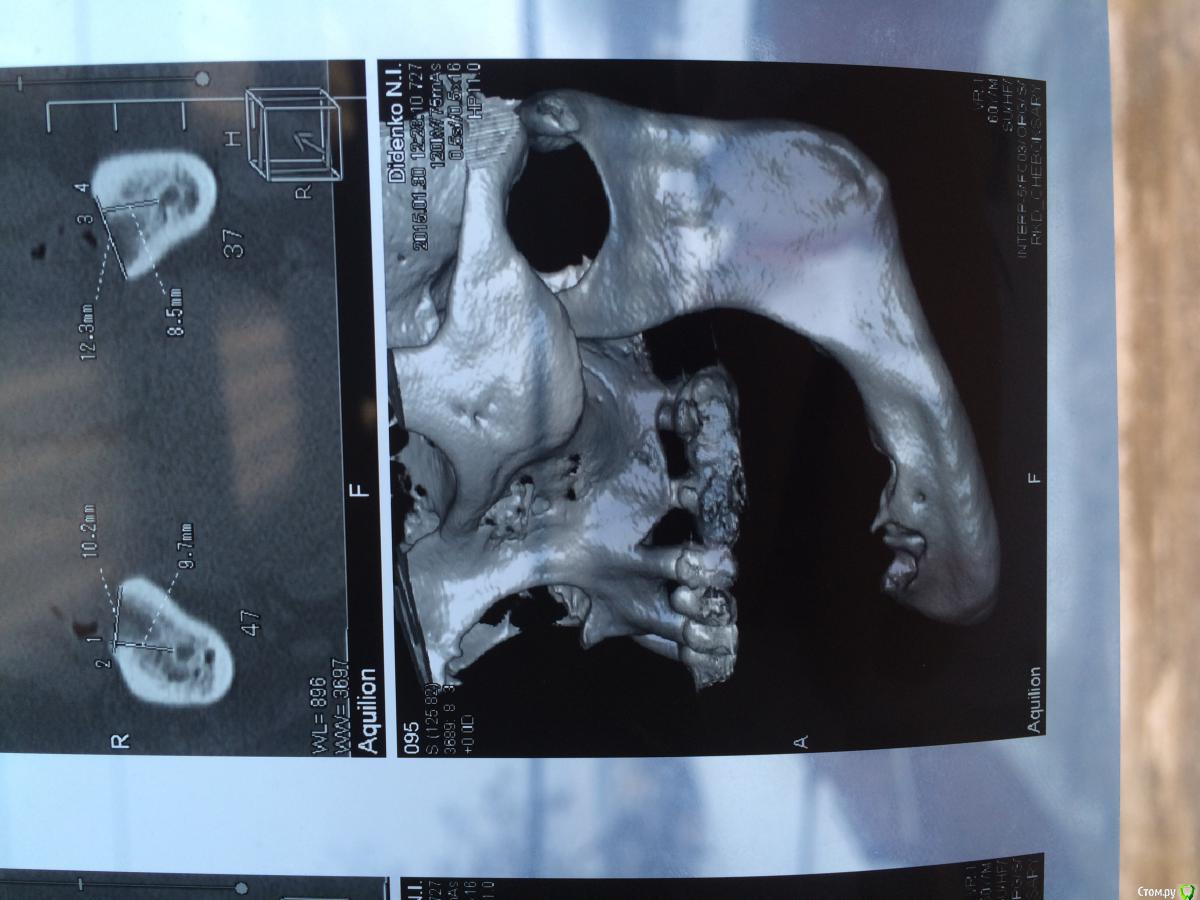

urseva19.05.10 Опубликовано 31 января, 2015 Поделиться Опубликовано 31 января, 2015 Коллеги, в каких позициях на ваш взгляд целесообразнее поставить имплантаты желательно без НКР ( пациент ограничен во времени) что бы в последствии протезироваться съемным протезом на локаторах? На верх не смотрите там все ясно Спасибо! Ссылка на комментарий

колесников Опубликовано 1 февраля, 2015 Поделиться Опубликовано 1 февраля, 2015 тут подойдёт постановка по типу ,,всё на 4ёх,, ,обходя ментальные.костные пики во фронте надо нивелировать и материал всётаки оставить. Ссылка на комментарий

faity Опубликовано 4 февраля, 2015 Поделиться Опубликовано 4 февраля, 2015 выровнить гребень и сделать НКР это не одно и тоже. для съемника на локаторах нужен одинаковый уровень винтов и биотип не менее 3-х мм. гребень можно просто выровнять до одинаковой высоты, ямы присыпать придется, десну можно выростить при необходимости.а почему именно локаторы? не хотите балку на 6-ти винтах? условия вроде позволяют Ссылка на комментарий

АнтонТЛТ Опубликовано 9 февраля, 2015 Поделиться Опубликовано 9 февраля, 2015 Потихоньку задумываюсь об этом. В области каких зубов думаете без нкр получиться?ширина достаточная, так что практически в любом месте можно поставить короткие имплантаты Ссылка на комментарий